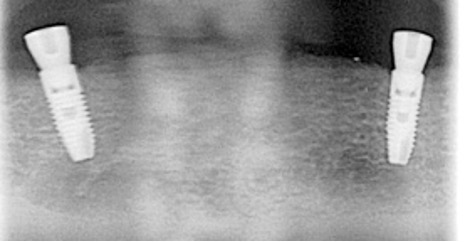

Implant bridges

Two missing teeth can be replaced by a single dental implant. This is often the case if there is not enough bone at both sites or the space is too narrow for two implants. It can also reduce the cost of treatment. As long as the bite forces are controlled and a strong implant is used these can be a very successful treatment.